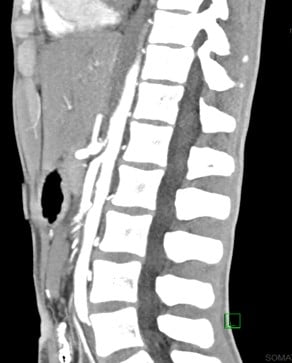

Computed tomography downloaded from Occupational Safety and Health

CT Scan

YouTube link for the initial CT scan is available at https://youtu.be/jG0J2b3EhhU.

Impression

Extensive air surrounded the esophagus and within the mediastinum, with dissecting along soft tissue planes, as described, suggestive of an esophageal perforation.

There is no free air in the abdomen. There is dilated stomach and proximal duodenum, with narrowing of the duodenum as it crosses the superior mesenteric artery (SMA). This can be seen with SMA syndrome in the proper clinical setting.